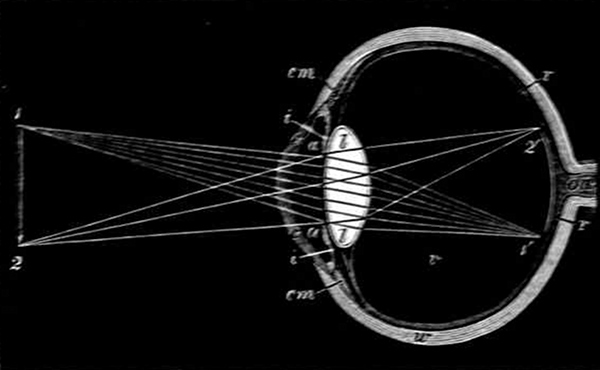

"Let us try to understand this before we go on to artificial glasses, for it will help us to explain how these glasses show us many things we could never see without them. Here are two pictures of the human eyeball (Figs. 10 and 11), one as it appears from the front, and the other as we should see the parts if we cut an eyeball across from the front to [Pg 30] the back. From these drawings we see that the eyeball is round; it only looks oval, because it is seen through the oval slit of the eyelids. It is really a hard, shining, white ball with a thick nerve cord (on, Fig. 11) passing out at the back, and a dark glassy mound c, c in the centre of the white in front. In this mound we can easily distinguish two parts—first, the coloured iris or elastic curtain (i, Fig. 10); and secondly, the dark spot or pupil p in the centre. The iris is the part which gives the eye its colour; it is composed of a number of fibres, the outer ones radiating towards the centre, the inner ones forming a ring round the pupil; and behind these fibres is a coat of dark pigment or colouring matter, blue in some people, grey, brown, or black in others. When the light is very strong, and would pain the nerves inside if too much entered the pupil or window of the eye, then the ring of the iris contracts so as partly to close the opening. When there is very little light, and it is necessary to let in as much as possible, the ring expands and the pupil grows large. The best way to observe this is to look at a cat's eyes in the dusk, and then bring her near to a bright light; for [Pg 31] the iris of a cat's eye contracts and expands much more than ours does."

Section of an eye looking at a pencil. (Adapted from Kirke.)

Section of an eye looking at a pencil. (Adapted from Kirke.)

c, c, Cornea. w, White of eye. cm, Ciliary muscle. a, a, Aqueous humour. i, i, Iris. l, l, Lens. r, r, Retina. on, Optic nerve. 1, 2, Pencil. 1´, 2´, Image of pencil on the retina.

"Now look at the second diagram (Fig. 11) and notice the chief points necessary in seeing. First you will observe that the pupil is not a mere hole; it is protected by a curved covering c. This is the cornea, a hard, perfectly transparent membrane, looking much like a curved watch-glass. Behind this is a small chamber filled with a watery fluid a, called the aqueous humour, and near the back of this chamber is the dark ring or iris i, which you saw from the front through the cornea and fluid. Close behind the iris again is the natural 'magic glass' of our eye, the crystalline lens l, which is composed of perfectly transparent fibres and has two rounded or [Pg 32] convex surfaces like an ordinary magnifying glass. This lens rests on a cushion of a soft jelly-like substance v, called the vitreous humour, which fills the dark chamber or cavity of the eyeball and keeps it in shape, so that the retina r, which lines the chamber, is kept at a proper distance from the lens. This retina is a transparent film of very sensitive nerves; it forms a screen at the back of the chamber, and has a coating of very dark pigment or colouring matter behind it. Lastly, the nerves of the retina all meet in a bundle, called the optic nerve, and passing out of the eyeball at a point on, go to the brain. These are the chief parts we use in seeing; now how do we use them?

"Suppose that a pencil is held in front of the eye at the distance at which we see small objects comfortably. Light is reflected from all parts of the surface of the pencil, and as the rays spread, a certain number enter the pupil of the eye. We will follow only two cones of light coming from the points 1 and 2 on the diagram Fig. 11. These you see enter the eye, each widely spread over the cornea c. They are bent in a little by this curved covering, and by the liquid behind it, while the iris cuts off the rays near the edges of the lens, which would be too much bent to form a clear image. The rest of the rays fall upon the lens l. In passing through this lens they are very much bent (or refracted) towards each other, so much so that by the time they reach the end of the dark chamber v, each cone of light has come to a point or focus 1´, 2´, and as rays of this kind have come from every point all over the pencil, [Pg 33] exactly similar points are formed on the retina, and a real picture of the pencil is formed there between 1´ and 2´."

"We will make a very simple and pretty experiment to illustrate this. Darkening the room I light a candle, take a square of white paper in my hand, and hold a simple magnifying glass between the two (see Fig. 12) about three inches away from the candle. Then I shift the paper nearer and farther behind the lens, till we get a clear image of the candle-flame upon it. This is exactly what happens in our eye. I have drawn a dotted line c round the lens and the paper on the diagram to represent the eyeball in which the image of the candle-flame would be on the retina instead of on the piece of paper. The first point you will notice is that the candle-flame is upside down on the paper, and if you turn back to Fig. 11 you will see why, for it is plain that the cones of light cross in the lens l, 1 going to 1´ and 2 to 2´. Every picture made on our retina is upside down.

"But it is not there that we see it. As soon as the [Pg 34] points of light from the pencil strike upon the retina, the thrill passes on along the optic nerve on, through the back of the eye to the brain; and our mind, following back the rays exactly as they have come through the lens, sees a pencil, outside the eye, right way upwards.

"This is how we see with our eyes, which adjust themselves most beautifully to our needs. For example, not only is the iris always ready to expand or contract according as we need more or less light, but there is a special muscle, called the ciliary muscle (cm, Fig. 11), which alters the lens for us to see things far or near. In all, or nearly all, perfect eyes the lens is flatter in front than behind, and this enables us to see things far off by bringing the rays from them exactly to a focus on the retina. But when we look at nearer things the rays require to be more bent or refracted, so without any conscious effort on our part this ciliary muscle contracts and allows the lens to bulge out slightly in front. Instantly we have a stronger magnifier, and the rays are brought to the right focus on the retina, so that a clear and full-size image of the near object is formed. How little we think, as we turn our eyes from one thing to another, and observe, now the distant hills, now the sheep feeding close by; or, as night draws on, gaze into limitless space and see the stars millions upon millions of miles away, that at every moment the focus of our eye is altering, the iris is contracting or expanding, and myriads of images are being formed one after the other in that little dark chamber, [Pg 35] through which pass all the scenes of the outer world!